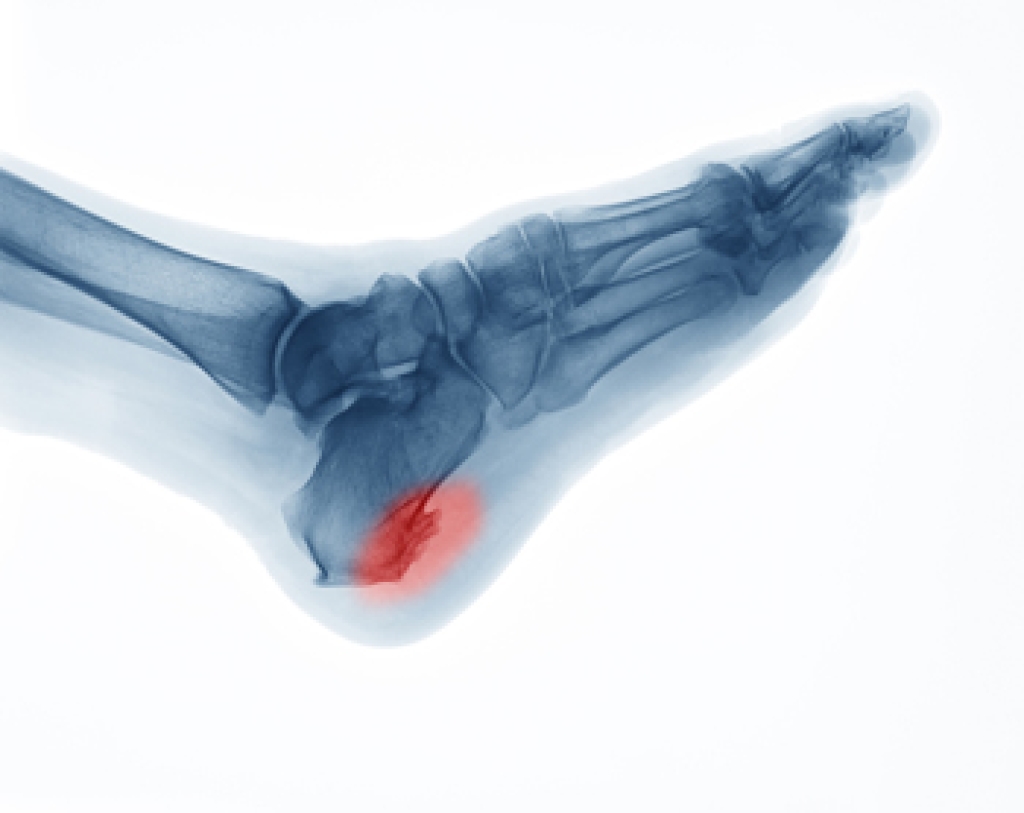

Tendonitis is common among people who incur an Achilles tendon injury. Heel and calf pain often accompany this ailment, and it can be uncomfortable. The Achilles tendon connects the calf muscle to the heel and may become torn from an injury. These can include overuse injuries from running on hard surfaces or increasing speed and distance too quickly while running. People who have arthritis may be prone to Achilles tendonitis, and it can affect older and middle-aged patients more than younger adults. Common symptoms are immediate heel pain and difficulty pointing and flexing the foot. Additionally, the area may be warm and tender to the touch. A proper diagnosis is needed to rule out the possibility of a fracture. If you have endured an Achilles tendon injury, it is suggested that a podiatrist be consulted who can effectively help you manage this condition.

The Achilles tendon is a tendon that connects the lower leg muscles and calf to the heel of the foot. It is the strongest tendon in the human body and is essential for making movement possible. Because this tendon is such an integral part of the body, any injuries to it can create immense difficulties and should immediately be presented to a doctor.